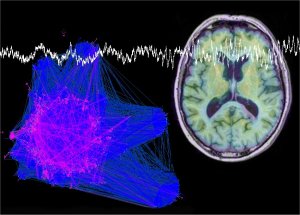

Los pacientes de la enfermedad de Alzheimer presentan en sus cerebros dos estructuras patológicas características: placas seniles compuestas principalmente por agregados delpéptido beta-amiloide y ovillos fibrilares intracelulares compuestos de la proteína tau anormalmente agregada y fosforilada.

El trabajo (llevado a cabo en el laboratorio de los profesores Fernando Valdivieso y María Jesús Bullido en el Centro de Biología Molecular «Severo Ochoa» CBMSO, y dirigido por el investigador Jesús Aldudo del Centro de Investigación Biomédica en Red sobre Enfermedades Neurodegenerativas CIBERNED) demuestra que la infección con el virus HSV-1 tiene como consecuencia la acumulación progresiva de la proteína tau hiperfosforilada en el núcleo de células neuronales humanas y neuronas primarias de ratón.

Los investigadores además constataron que tau fosforilada se localiza en la maquinaria donde tiene lugar la replicación del ADN viral, indicando un posible papel de esta proteína en la replicación del virus. Estudios con células que no expresan tau revelaron que esta proteína no es esencial para el crecimiento del virus. Sin embargo, la acumulación de tau fosforilado potencialmente neurotóxico podría desencadenar la muerte neuronal.